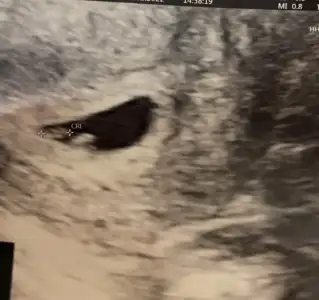

Aynen bende erkek gibi gördüm. Şöyle iki doğru resimleri göstereyim. 3-4 bebek bu şekilde tahmini doğru çıktıBenim 10+3 günlük ama doktora göre 10+5 ve 10+6 dedi çıkıntıdan dolayı bana erkek gibi geldi birde siz bakar mısnız rica etsem

İlk haftalarda her 2 cinsiyette de çıkıntı oluyormuş sonra kızlarda içeri giriyormuş diye okudum benimki de baya küçük hafta olarak sanırım daha belli olmaz doktorda erken dedi çünkü sorduğumda cinsiyet tahmini için ama ramziye göre de erkek tarafındaydı benim meselaAynen bende erkek gibi gördüm. Şöyle iki doğru resimleri göstereyim. 3-4 bebek bu şekilde tahmini doğru çıktı